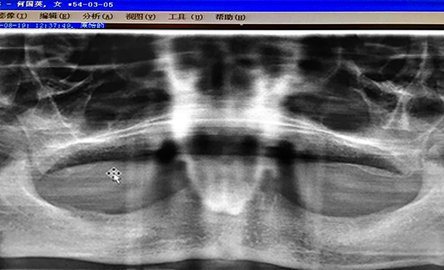

来院后,周海燕医生为其检查,从口腔全景片、全口CT检查发现,何女士由于多年的牙周炎,长期缺牙佩戴活动假牙,导致牙槽骨严重萎缩,骨量不足,壁薄,增加了治疗难度,普通的口腔医生无法进行这种高难度的全口无牙种植。

种植前全景片